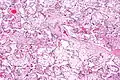

Micrograph of villous immaturity. H&E stain. | |

Immature chorionic villi are larger and have more central blood vessels; thus, the diffusion distance for gas and nutrient exchange is larger and, therefore, placental function is impaired.